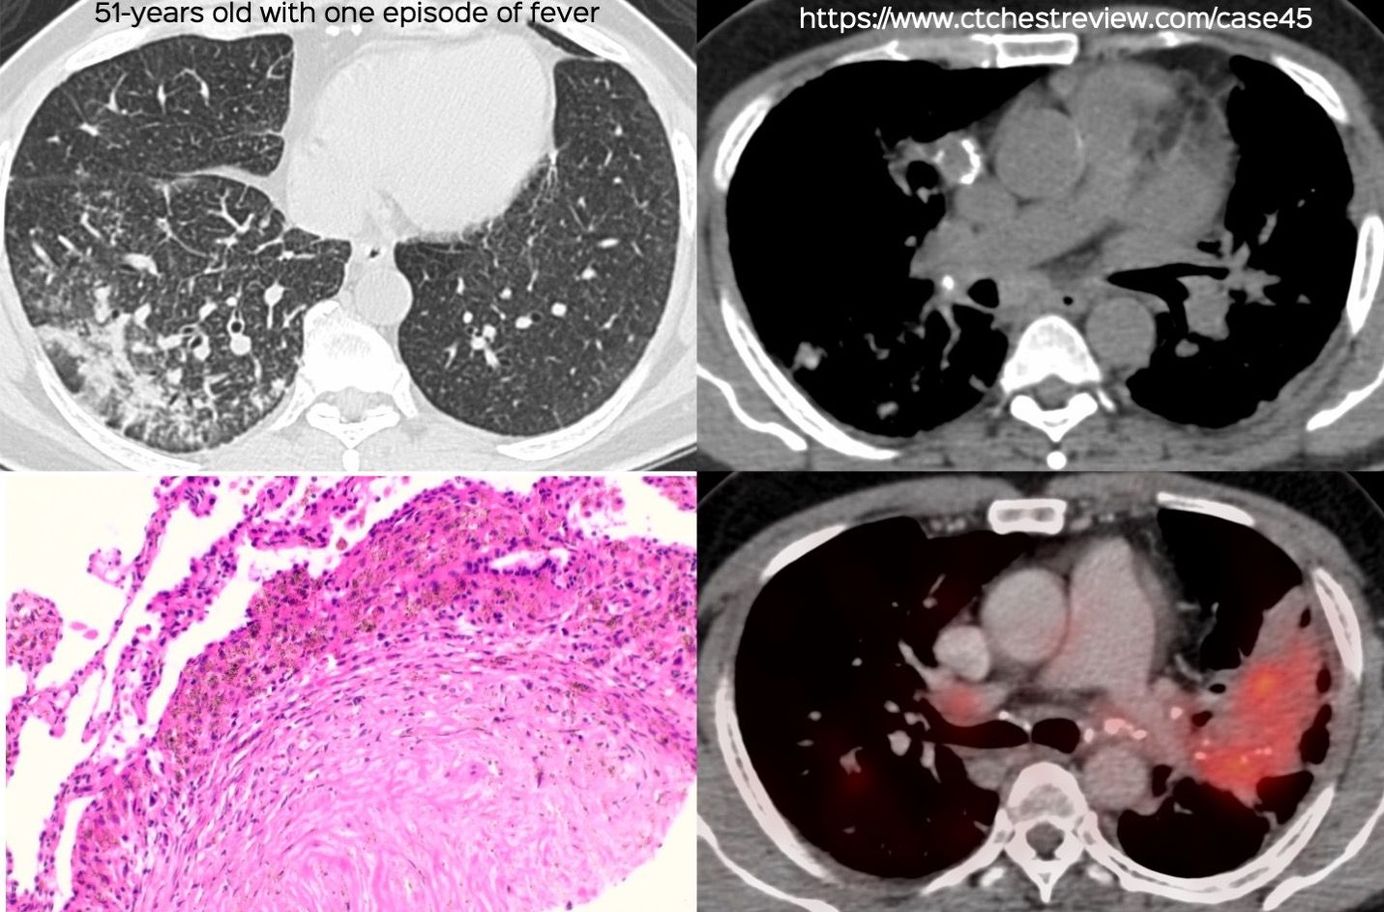

Case of the Day 112 - The Cognitive Bias of Inattentional Blindness

We need to up our game and pick up all the findings that exist by paying attention to different parts of the chest, scrolling slow and fast and asking ourselves each time whether every area is normal or not